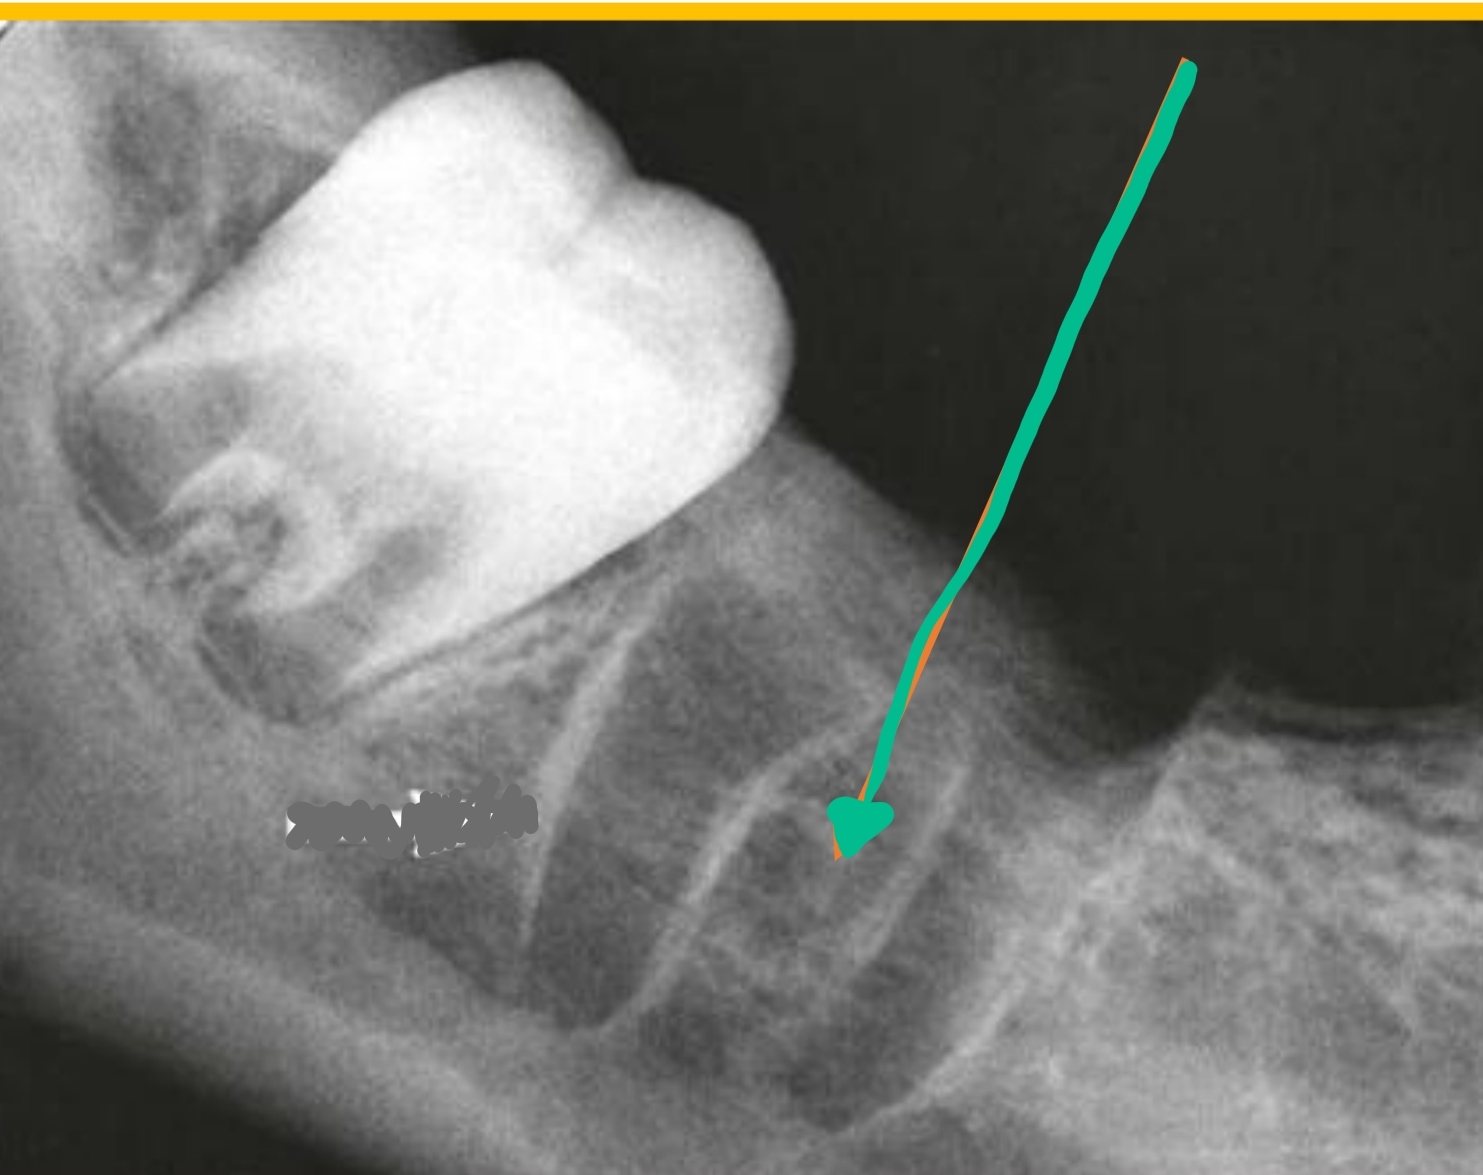

Opening between 1st and 2nd premolars (mental nerve)

Mental Foramen